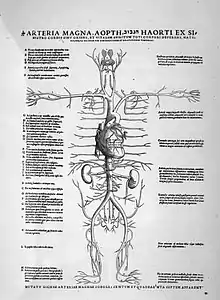

En 1543, Andreas Vesalius publie ses travaux De humani corporis fabrica[3],[4] dans lesquels la théorie physiologique de Galien fut adaptée à ses nouvelles observations[5].

L'italien Realdo Colombo est un des premiers à décrire parfaitement la circulation pulmonaire. C'est Andrea Cesalpino (1519-1603) qui utilise le premier le terme de « circulation » et qui en attribue le rôle au cœur, alors que l'on pensait jusqu'ici que le mouvement du sang dépendait de la pulsation des artères. Finalement William Harvey (1578-1657), élève de Fabrice d'Acquapendente (1537-1619), fait la première description complète du système circulatoire, dans son ouvrage Exercitatio Anatomica de Motu Cordis et Sanguinis in Animalibus de 1628. Il décrit notamment le sens de circulation et le rôle exact des valvules veineuses, et établit que la circulation est importante (plusieurs litres par minute) alors qu'on la croyait au goutte-à-goutte. L'idée première en reviendrait à Walter Warner[11]. Marcello Malpighi identifie pour la première fois les capillaires au microscope en 1661.